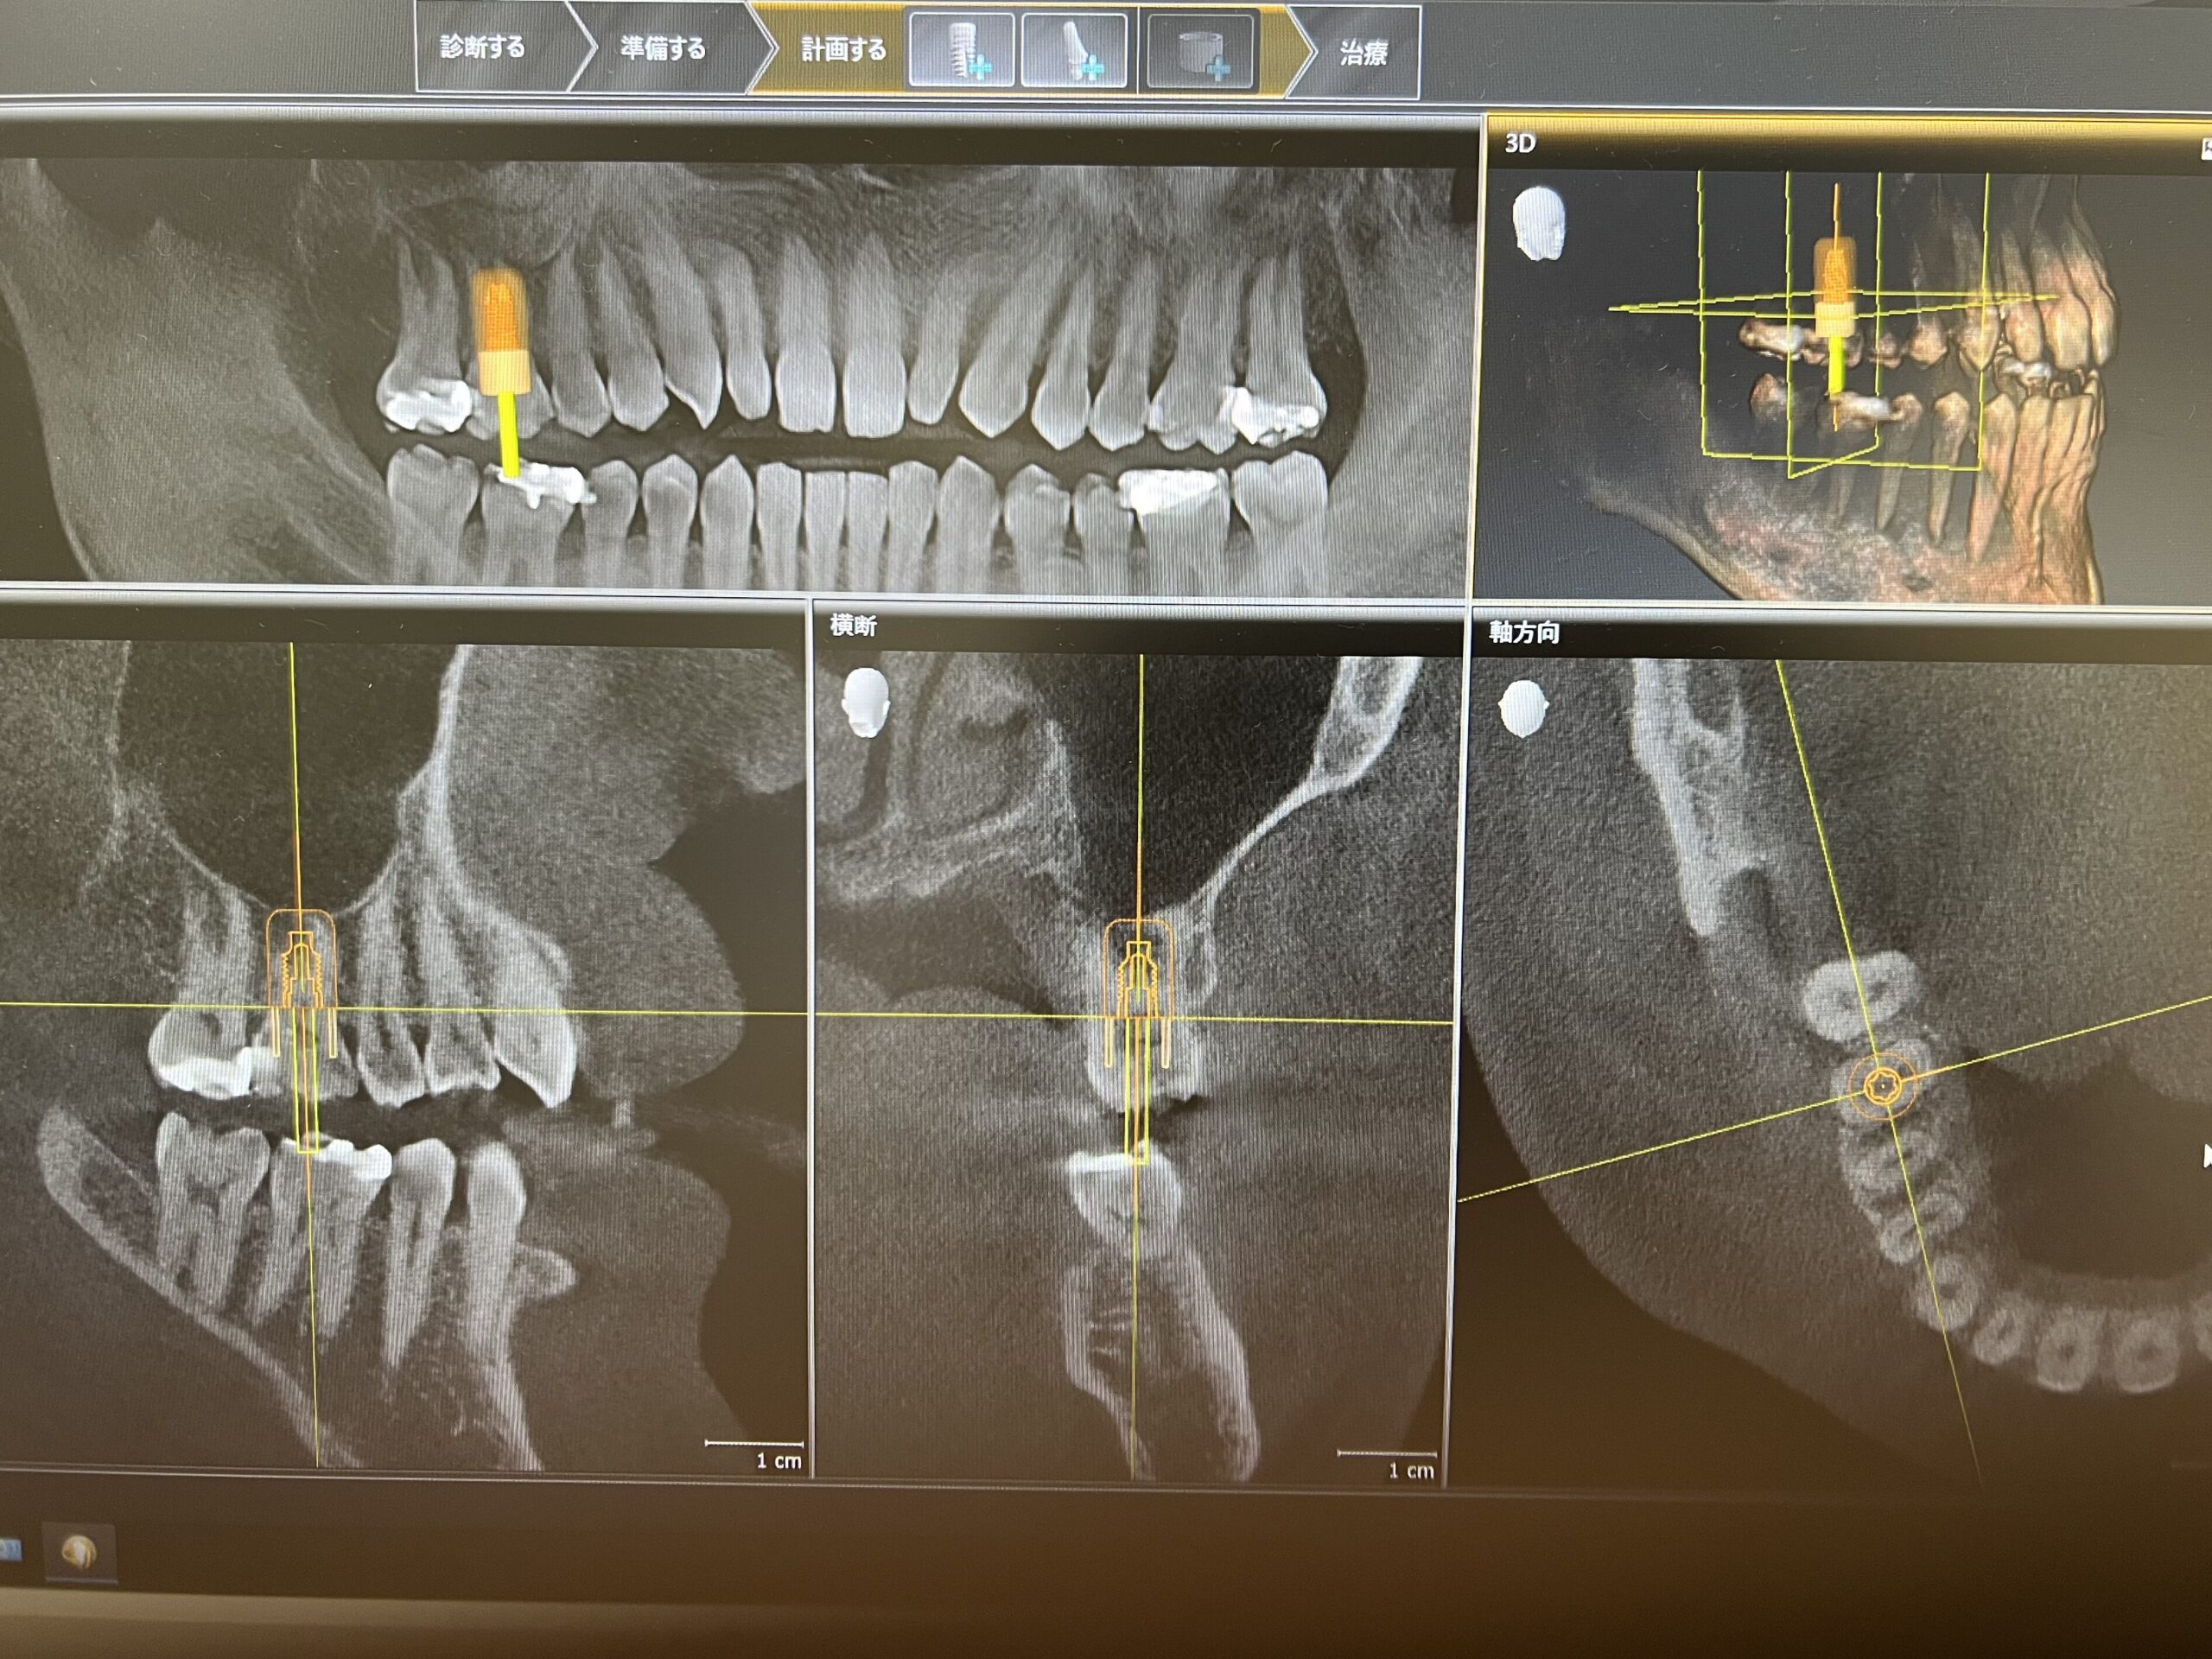

インプラント

CTで骨の状態を確認し、各インプラントメーカーのインプラントの長さや太さなどの形状を当てはめてシミュレーションするソフトが内蔵されております。

そのデータとセレック(←押して頂くと審美歯科とセレックのページへ)で作成した失った歯の形をコンピューター上でマッチングさせ、インプラントを安全に埋入するためのガイド(セレックガイド)を作製できます

このCT撮影のデータとお口の中のデータを合わせてインプラント治療のシミュレーションを行った後に、その計画通りにインプラントを入れるためのインプラントガイドも作製可能です😊